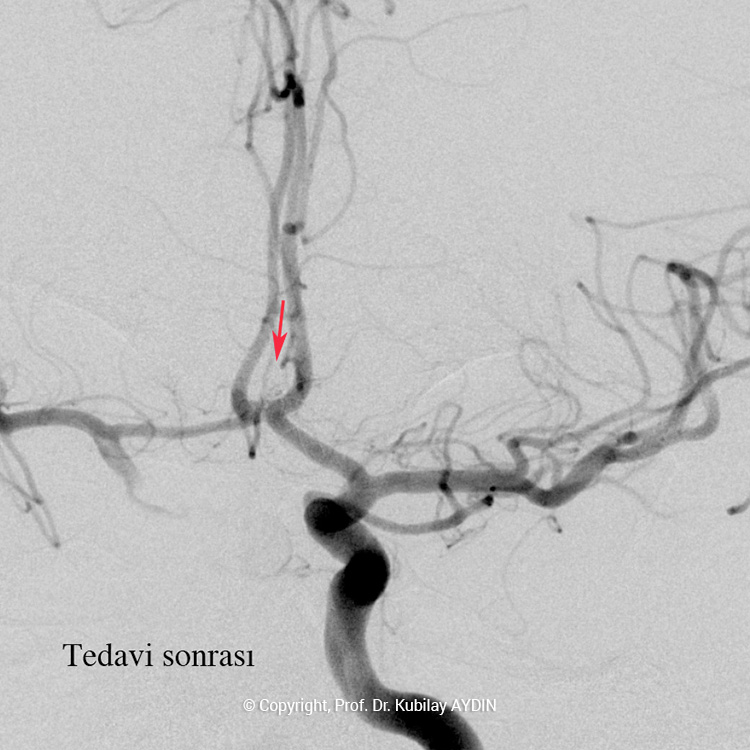

Geniş boyunlu anevrizmaların stent kullanılarak koillerle kapatılması işlemine “stent-yardımlı koilleme” adını veriyoruz. Bu işlemin ilk aşamasında anevrizmanın boynunu örtecek şekilde damar içine bir metal kafes (stent) yerleştirilerek, bir sonraki aşamada anevrizma kesesi içine konulan koillerin damar içine sarkması önlenir. Yani, burada stentin görevi, anevrizma içine doldurduğumuz koil adı verilen tellerin, damar içine sarkmasını önlemektir. Stent-yardımlı koilleme, geniş boyunlu anevrizmaların kapalı yöntemle tedavisinde tercih edilen bir yöntemdir.

Yaptığımız bilimsel araştırmalar sonucunda, stentlerin kan akımını yönlendirici etkilerinin de olduğu ve stentlerin bu özellikleri sayesinde tedavi edilen geniş boyunlu anevrizmaların tekrar oluşmasını engelleyebildiğini saptadık (Aydin Kubilay, et al. American journal of Neuroradiology 2015;36:1934-1941). Hızlı akan bir nehir üzerine kurulmuş baraj seti gibi, stentler de kan akımının anevrizma içine basınçla ulaşmasını engeller ve kapatılan anevrizmanın tekrar açılmasını önler. Günümüzde, çok geniş boyunlu ve bir çok damarın içinden çıktığı en kompleks anevrizmaları dahi, stent yardımlı koilleme tekniği uygulayarak başarıyla tedavi edebiliyoruz. Anevrizma tedavisinde kullandığımız stentler, damar duvarına zarar vermeyecek şekilde yumuşak yapıda ve vücud ile tam uyumlu, ileri teknoloji ile üretilmiş cihazlardır.

Stent yardımlı koilleme tekniği ile anevrizma tedavisinde, anevrizmanın yerleştiği atardamar içerisine stent açılması için bir kateter yerleştirilir. Eş zamanlı olarak, anevrizma kesesi içerisine koilleme amaçlı farklı bir kateter yerleştilir. Damar içerisine bir stent açıldıktan sonra, anevrizma içerisideki kateterden gönderilen platinden yapılmış çok yumuşak yapıda koillerle anevrizma kesesi doldurulur. Stent, anevrizma içeriside bırakılan koillerin damar içine sarkmasına engel olur. Koilleme işlemine, anevrizma koillerle tamamen doldurulana ve anevrizma içine kan girmeyene kadar devam edilir.